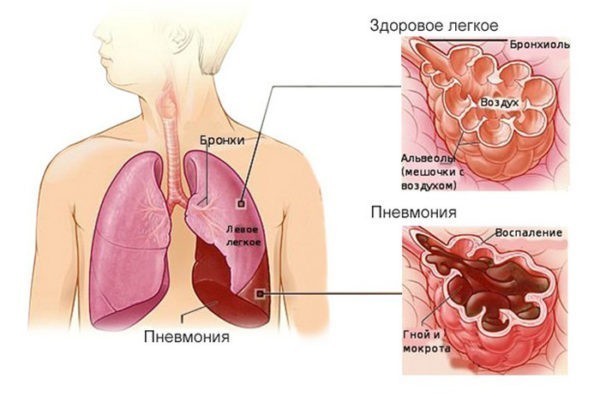

Пневмония – это острое инфекционное воспаление нижних дыхательных путей, которое характеризуется инфильтрацией легких (точнее – нижних дыхательных путей) воспалительной жидкостью и признаками воспаления. Что это значит? Прежде всего, это значит, что развитие пневмонии связано с наличием в дыхательных путях инфекционных агентов – бактерий, иногда вирусов или грибков, простейших.

Что такое нижние дыхательные пути? Это альвеолы (микроскопические мешочки, в которых происходит газообмен) и мелкие бронхи. Обязательным критерием пневмонии будет поражение альвеол, если у больного поражены только бронхи, то тогда это не пневмония, а бронхит или бронхиолит. Однако, наличие бронхита, трахеита или ларингита (воспаление бронхов, трахеи или гортани) не исключает поражение альвеол и соответственно наличие пневмонии.

Инфильтрация – это наличие воспалительной жидкости, которая состоит из продуктов крови, белков, клеток организма и бактерий, в просвете альвеол. Данная инфильтрация хорошо видна при проведении рентгенологического исследования и слышна врачу в виде специфических хрипов при выслушивании легких. Также пневмония сопровождается признаками воспаления, в том числе интоксикацией и повышением температуры, кашлем с возможным отхождением мокроты и другими симптомами.